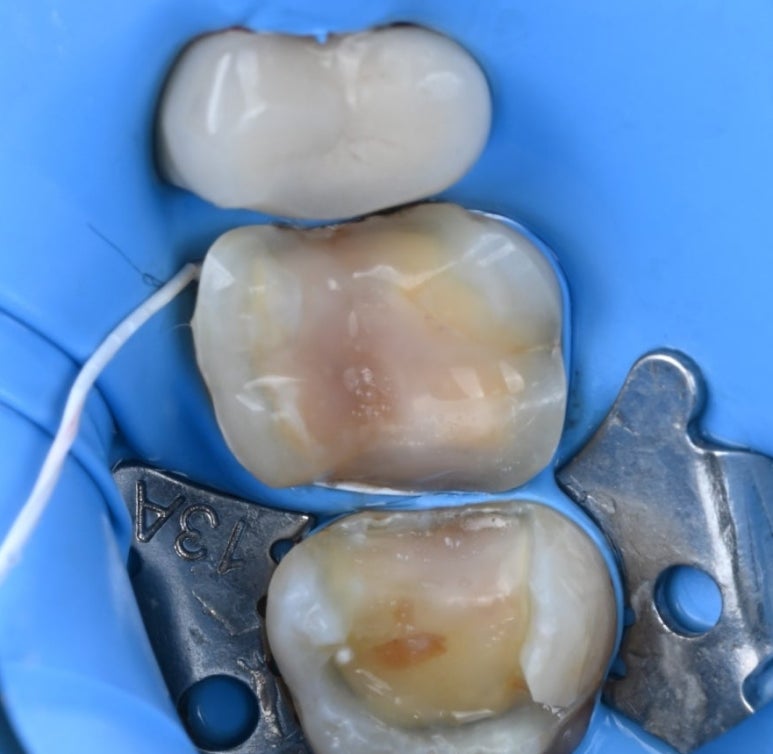

25.11.11 금인레이 제거 후 모습

앞쪽 어금니는 인레이를 제거해 보니

충치 범위가 넓어, 치아의 씹는 면을

전체적으로 보호해 주는

'세라믹 오버레이(Overlay)'를 적용하기로

결정했습니다.

25.11.11 러버댐 장착 후 레진 코팅을 시행한 모습

레진 코팅(Resin Coating)

본을 뜨기 전, 노출된 상아질을

레진으로 얇게 코팅하여 신경을 보호하고

접착력을 극대화합니다.

이 과정을 거치면 치료 후 시린 증상이 현저히 줄어듭니다.